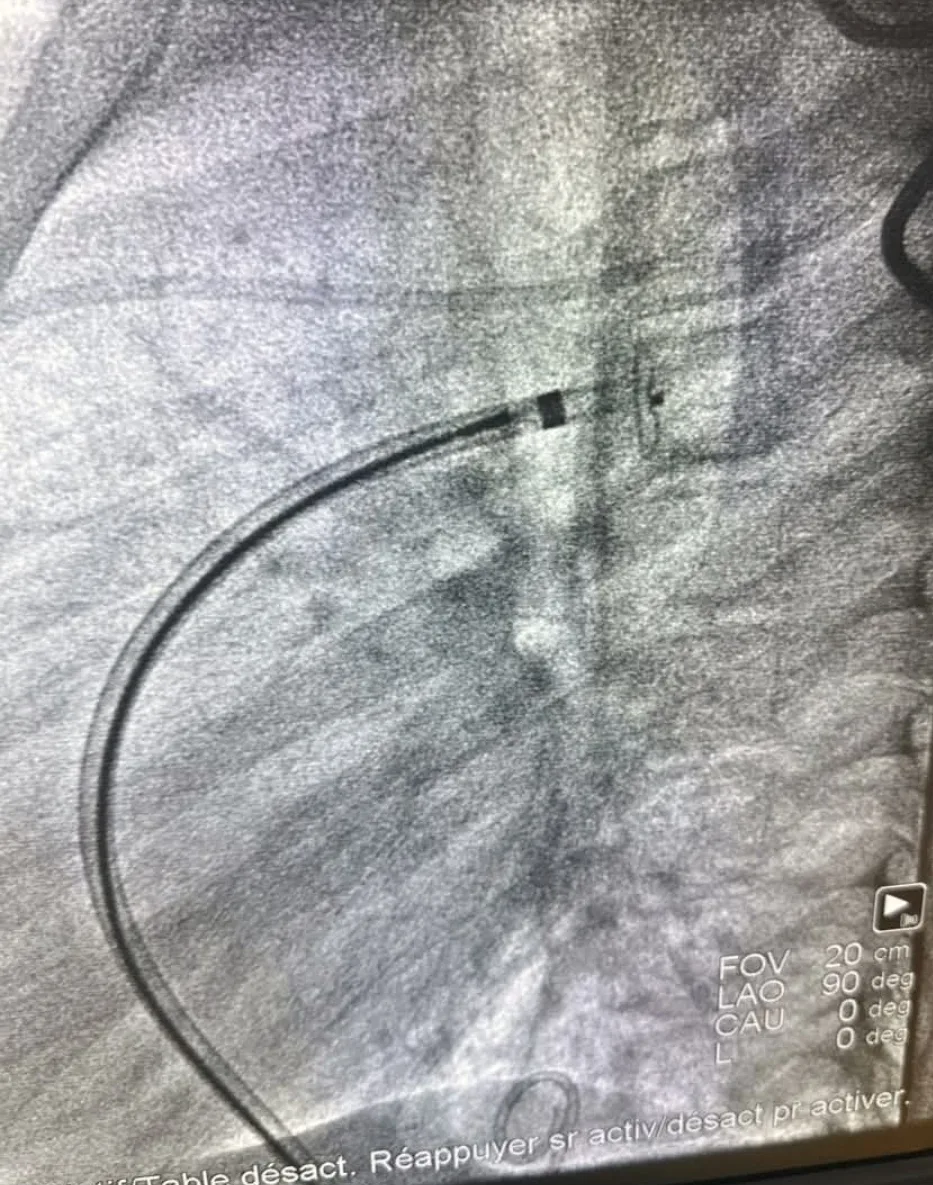

وأفاد البيان بأن هذه المبادرة تأتي في إطار اتفاقية التعاون والشراكة بين جهة الشرق وجهة الشرق الكبير بفرنسا (Grand Est)، مضيفاً أن القافلة اعتمدت أحدث التقنيات الطبية المعترف بها عالمياً، واستفاد من خلالها ثلاثة أطفال، حيث أكد الطاقم الطبي أن حالتهم الصحية جيدة وتعرف تحسناً مستمراً.

ويشير البيان إلى أن هذه المبادرة تمثل خطوة مهمة لتطوير خدمات قسطرة القلب للأطفال بجهة الشرق بصفة خاصة وبالمغرب عموماً، موضحاً أن هذه التقنية تعتبر أنجع مقارنة بالمقاربات الأخرى لعلاج التشوهات الخلقية لدى الأطفال، كما أنها من التقنيات النادرة التي تُعتمد بالمغرب.